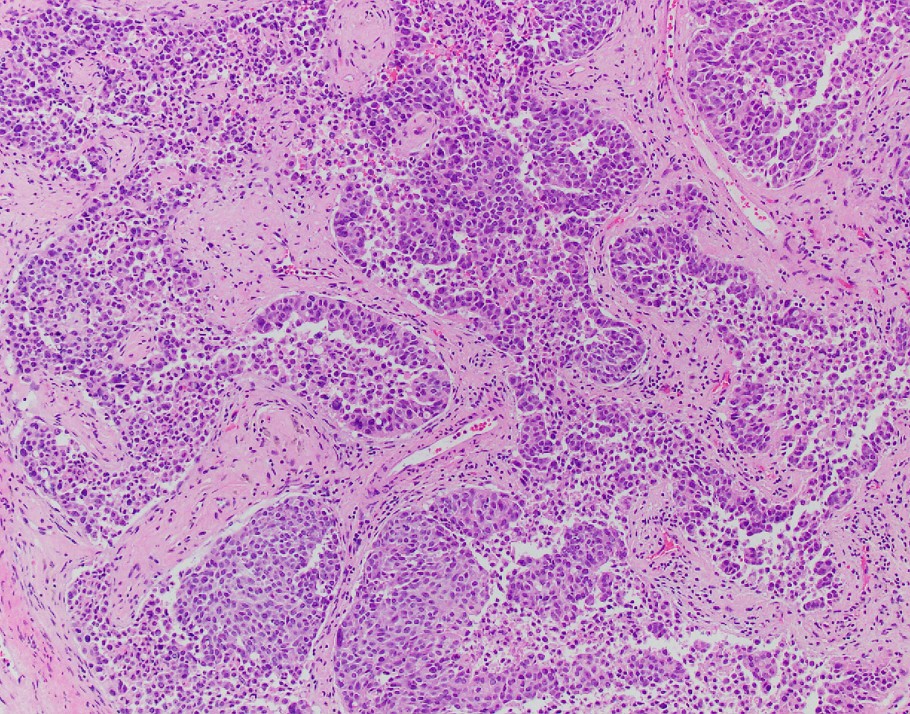

Explanation: INI-1 (SMARCB1)-deficient sinonasal carcinoma, currently listed as a subtype of sinonasal undifferentiated carcinoma (SNUC) in the current WHO Classification of Head and Neck Tumors, is a poorly differentiated sinonasal carcinoma defined by loss of nuclear INI-1 expression due to SMARCB1 deletion (1). Histologically, they have a definitive (adeno)carcinoma appearance unlike other INI-1-deficient tumors such as epithelioid sarcoma and atypical teratoid/rhabdoid tumor. INI-1-deficient sinonasal carcinoma shows islands of eosinophilic/oncocytoid and plasmacytoid carcinoma cells with variable glandular differentiation to include focal intracellular/intraluminal mucin production, and may also show a basaloid appearance (2). INI-1 (SMARCB1)-deficient sinonasal carcinoma typically shows expression of CK7. In one report 3 of 10 showed p40 expression, 4 of 12 examples showed CDX2 expression, and 3 of 12 showed CK20 expression (3). Variable/weak expression of neuroendocrine markers has been described. INI-1 (SMARCB1)-deficient sinonasal carcinoma is negative for high-risk HPV and EBV and is negative for S100 protein expression.

The differential diagnosis of INI-1 (SMARCB1)-deficient sinonasal carcinoma includes high-grade non-intestinal sinonasal adenocarcinoma, myoepithelial carcinoma, nonkeratinizing squamous cell carcinoma, mucosal melanoma, etc. All of the entities in the differential diagnosis, except a proportion of myoepithelial carcinomas, retain INI-1 expression. Myoepithelial carcinoma, unlike INI-1 (SMARCB1)-deficient sinonasal carcinoma, should express S100 protein and other myoepithelial markers (3). Recently the morphologic spectrum of INI-1 (SMARCB1)-deficient sinonasal carcinomas has been expanded to included examples with yolk-sac-like areas that have also shown limited glypican-3, SALL4, and HepPar-1 expression, adding germ cell tumor and metastatic hepatocellular carcinoma to the differential diagnosis (3).